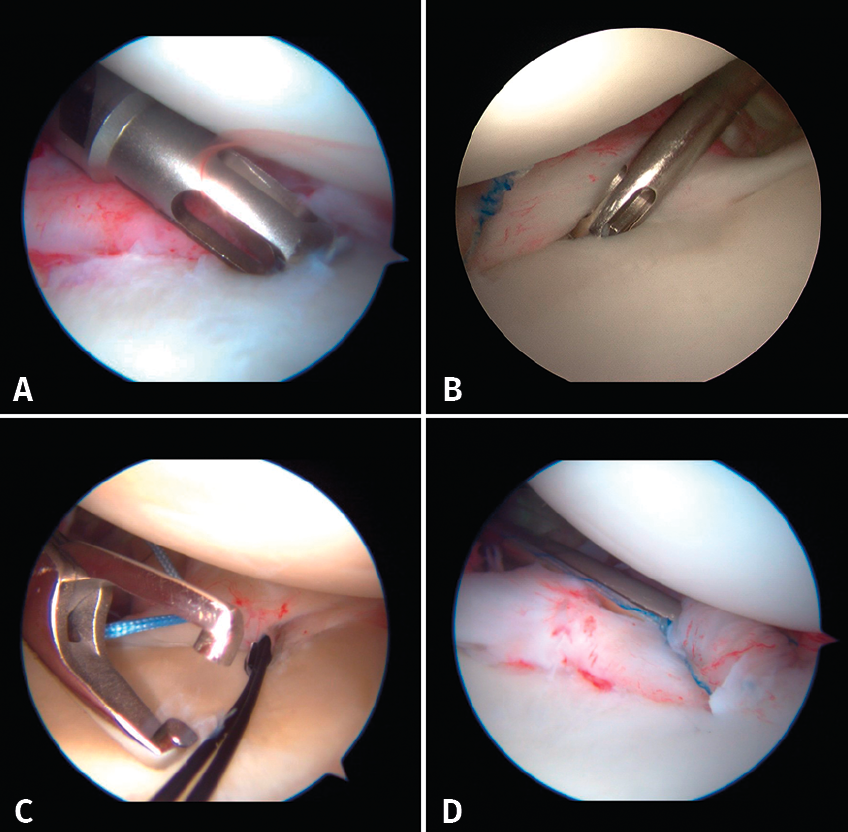

Once the Bankart lesion has been confirmed, we detach and mobilize the capsulolabral complex from the glenoid neck with arthroscopic rasps and/or dissectors until satisfactory and subscapular fibers are visualized (Figure 7). Before implant placement, it is necessary to perform decortication of the anterior glenoid neck using a 4-mm synoviotome. Repair is started after this step, always working from lower to upper.

Figure 7. Detachment and mobilization of the labrum.

The implants are to be placed at 45º from the joint surface adjacent to the margin of the anterior cartilage, taking care not to medialize them over the neck of the glenoid cavity (Figures 8A and B). We start with the lowest implant; depending on the extent of the lesion, we will need 3, 4 or 5 implants spaced 3-5 mm apart.

Capsulolabral repair can be carried out in different ways, since a number of suture passer systems are available: indirect nitinol devices (these require two steps, but are less damaging to the tissues) or direct passer forceps (involving a single step, but causing more damage).

If a direct system is used, we pass direct penetrating-suture retrieval forceps from anterior to posterior, tunnelling the tissue to be sutured and taking one of the implant threads for knotting to the post. This in all cases will be the thread passing through the tissue, and we try to keep the knot of the thread anterior to the reconstructed tissue without friction against the humeral joint surface. This same step can be made with indirect passer forceps, tunnelling a nitinol wire through the tissue (Figure 8C), allowing us to grasp and then knot one of the implant threads (Figure 8D).

Figure 8. A: placement of implants; B: placement of implants; C: passing of indirect forceps preloaded with a nitinol wire; D: knotting of the thread.